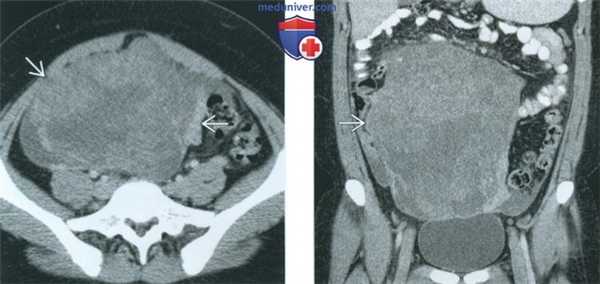

(Слева) При КТ с контрастным усилением в аксиальной плоскости у девушки 15 лет с пальпируемой в животе опухолью в тазу выявляется объемное образование, неравномерно накапливающее контрастное вещество.

(Справа) При КТ с контрастным усилением в корональной плоскости у той же пациентки в тазу видна опухоль, неравномерно накапливающая контрастное вещество. Полученное изображение в отсутствие жировой ткани и очагов обызвествления неспецифично. При патологоанатомическом исследовании диагностирована незрелая тератома высокой степени злокачественности.